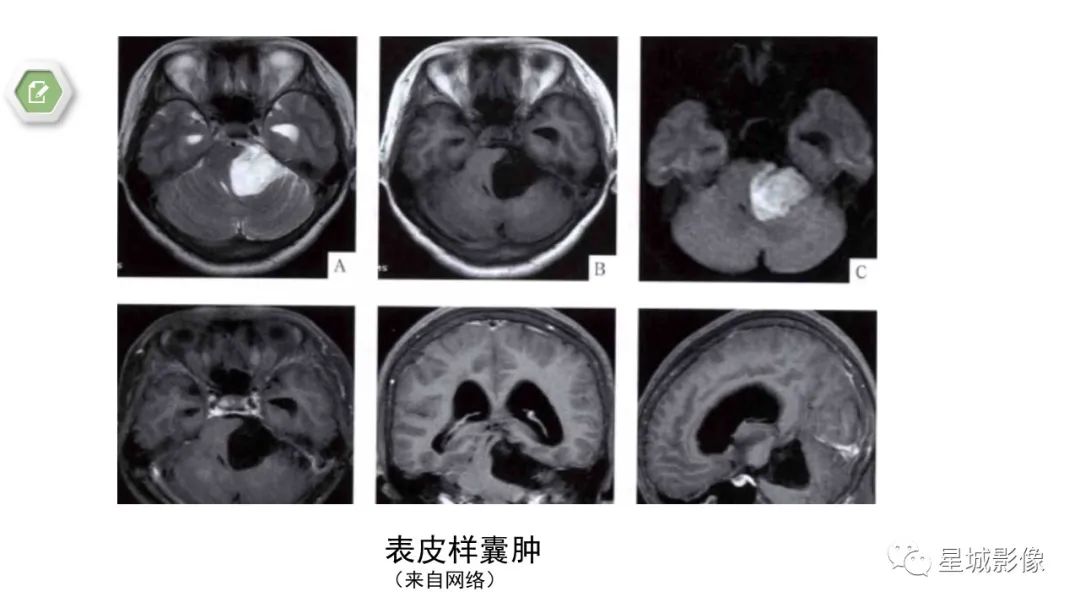

【病例】颅内成熟性囊性畸胎瘤1例MR影像表现-4

【病例】颅内成熟性囊性畸胎瘤1例MR影像表现-5

【病例】颅内成熟性囊性畸胎瘤1例MR影像表现-6